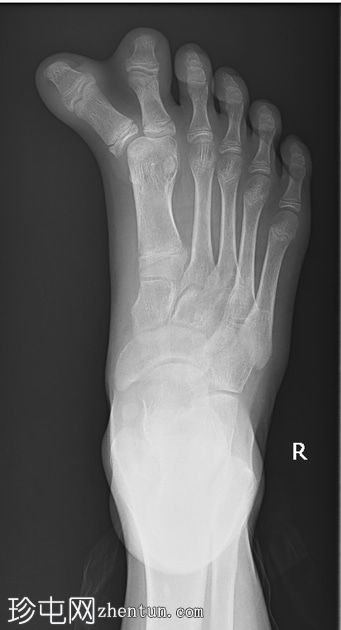

术后

X线片

正位片

侧位片

影像

显示足部骨骼排列正常;然而,第一跖跗关节处可见软组织肿胀,且第一跖骨增宽。这些特征与术后切除多余的轴前多趾畸形相符。